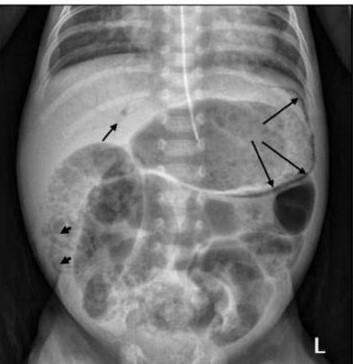

A

Neumoperitoneo : Estadio lllB

-“ Signo del balón de rugby “

10

Estadio ll B de Bell : neumatosis + gas en sistema venoso intrahepático